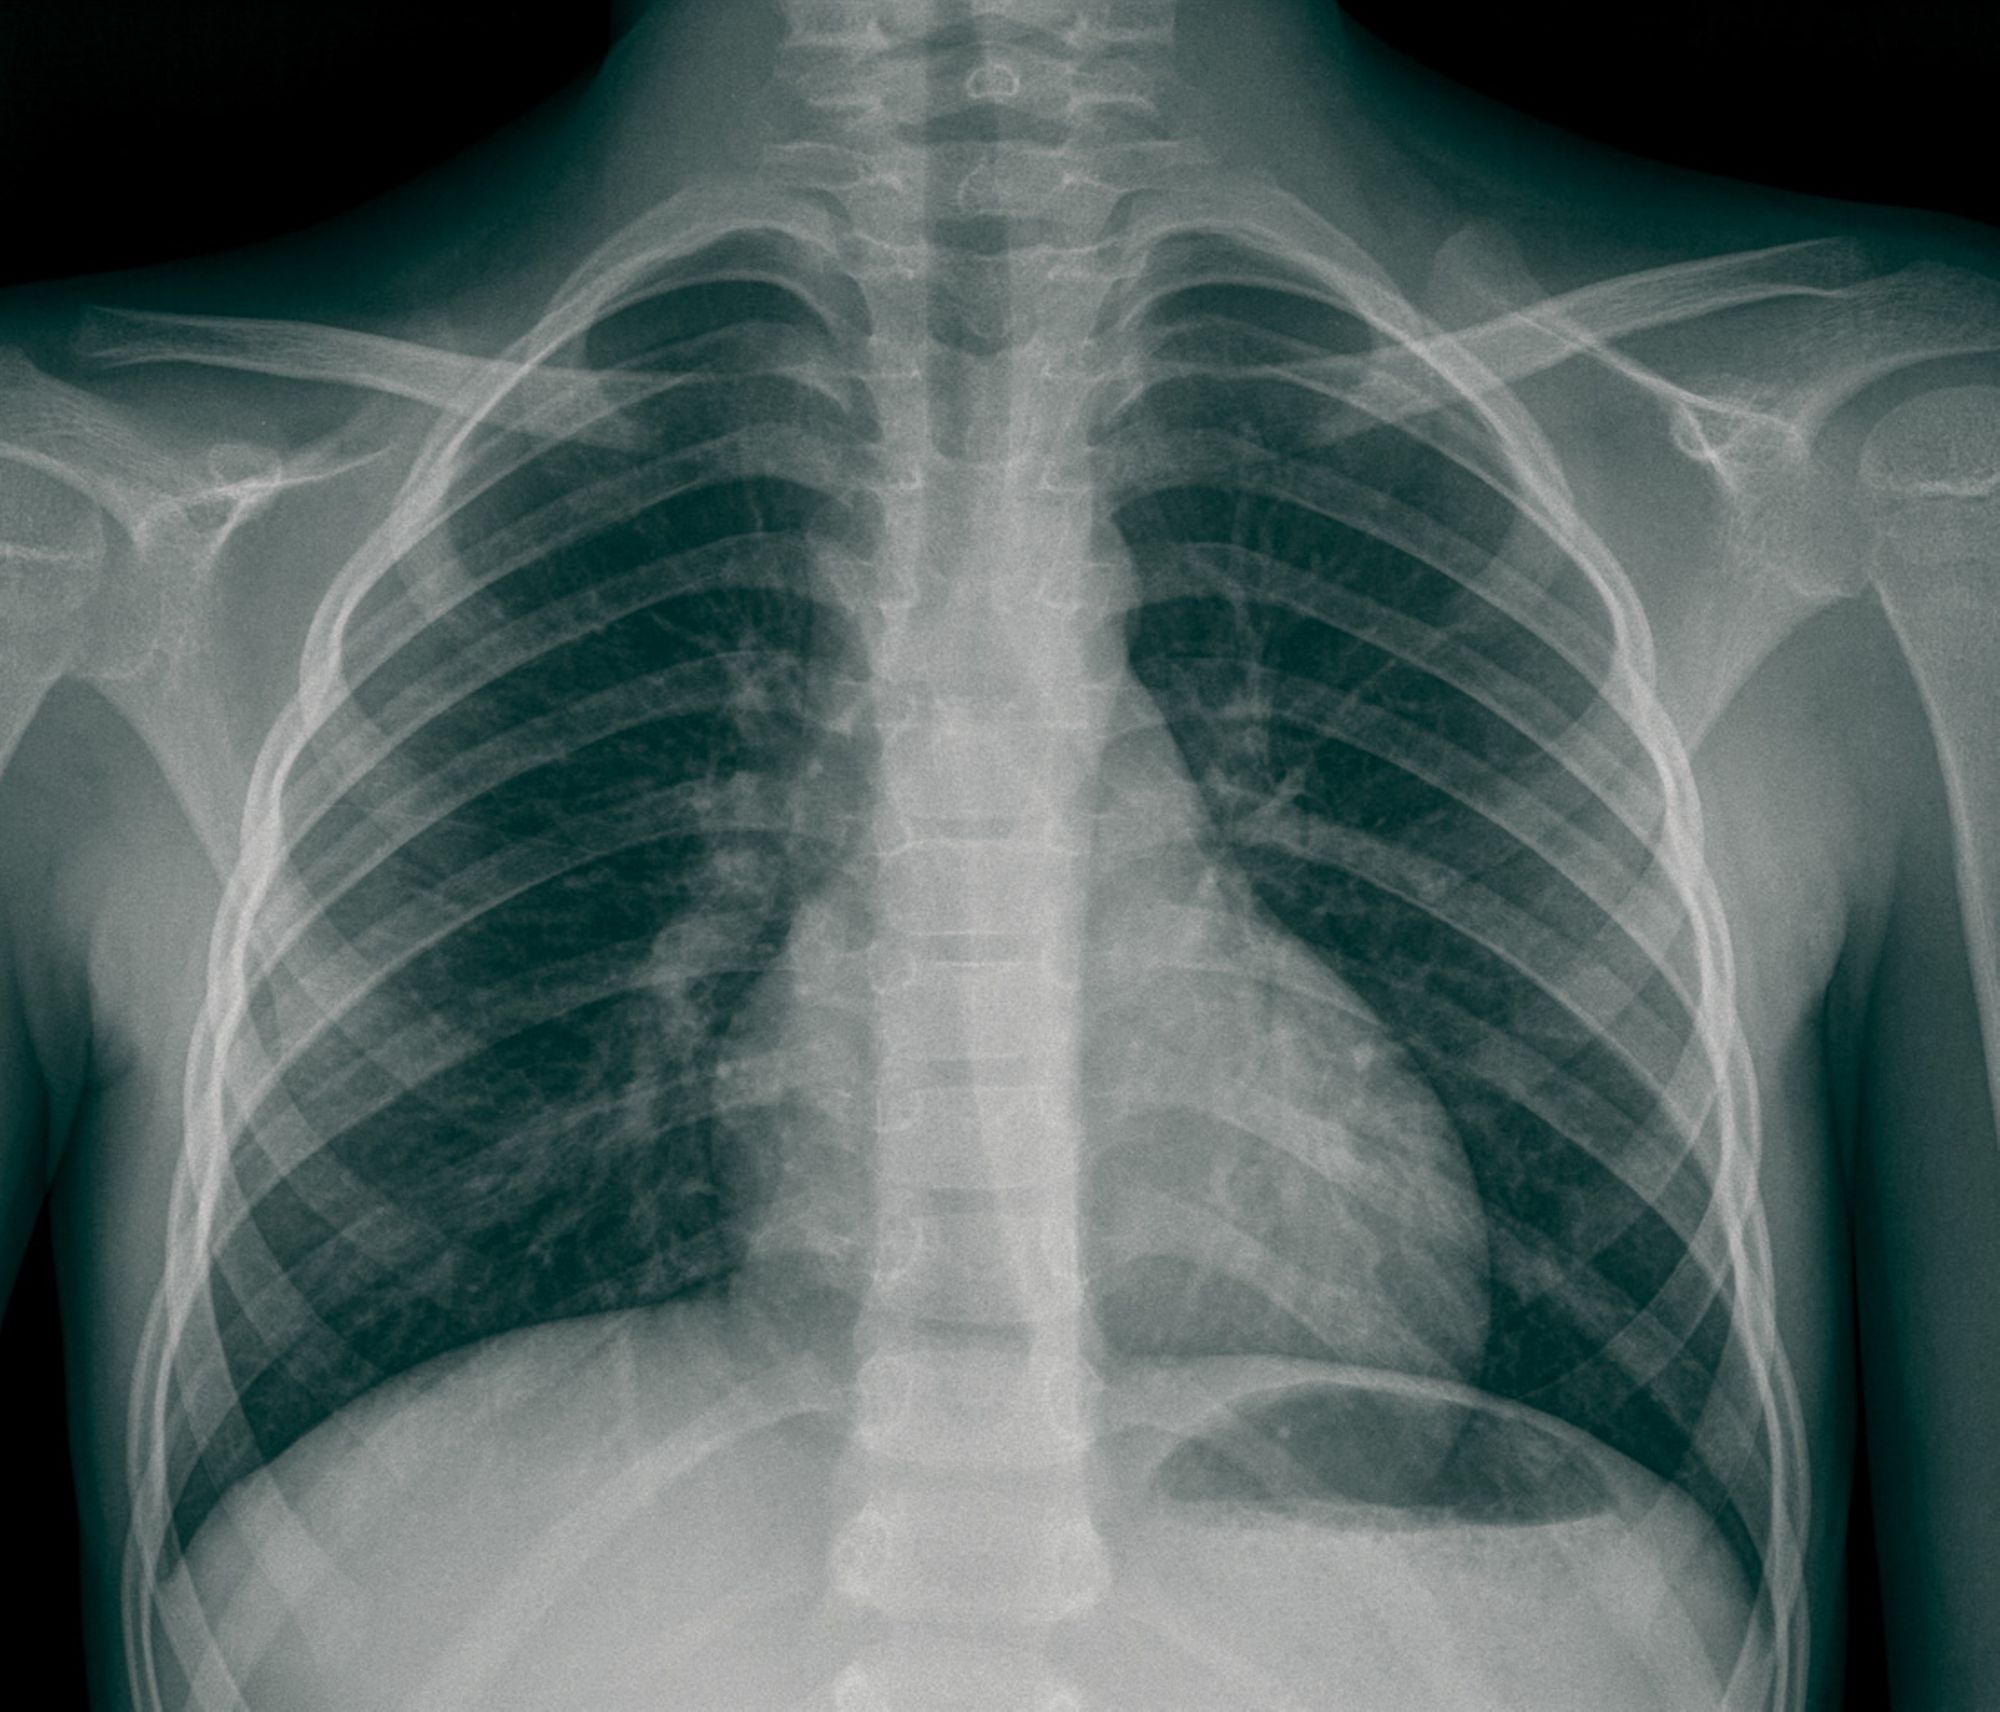

Radiographie numérisée

La radiologie conventionnelle utilise les rayons X pour obtenir des images du corps humain. C’est un examen très faiblement irradiant. Les clichés obtenus sont appelés radiographies. Nous réalisons à l’hôpital Saint Joseph tous types de radiographies.